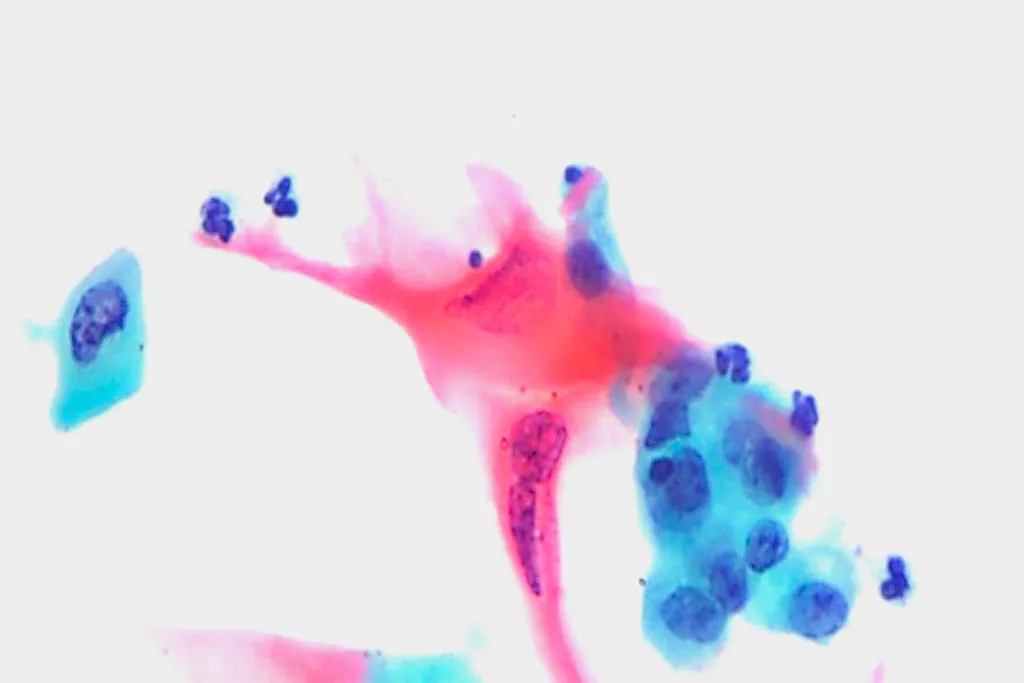

Fotogalerij9

9. Beelden ontvangen van de afdeling Cytopathologie, Llandough Hospital, Wales